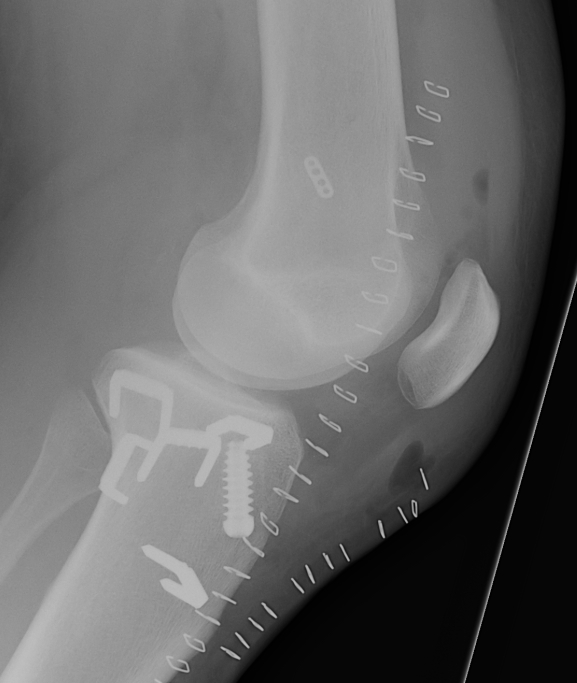

Xray following PCL reconstruction, LCL and politeus reconstruction. CT demonsrating popliteus and LCL tunnels